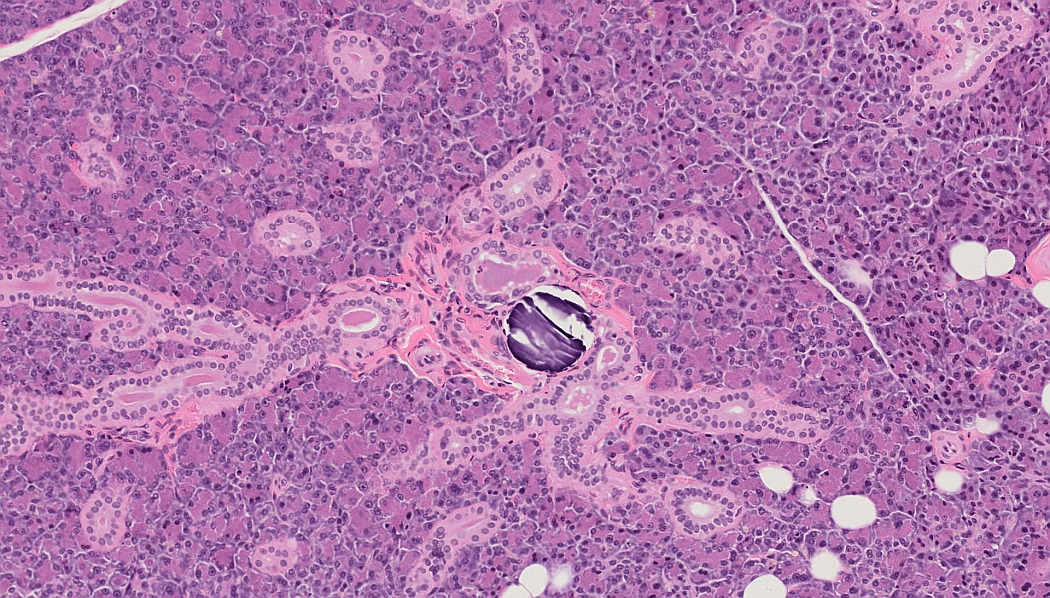

Guess What: Morphological species- and gender-specific peculiarities of laboratory animals

Glands of the Head and Neck Region